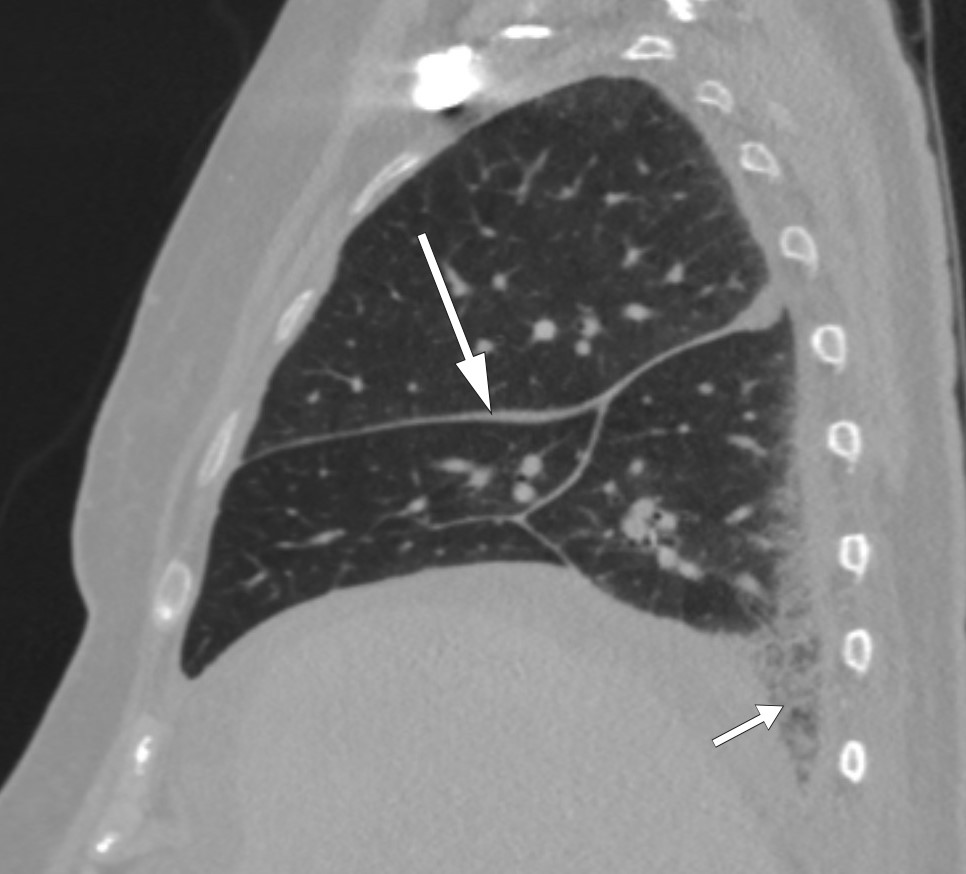

In addition to the perinephric changes, there were notable findings on CT thorax (Fig. 2) and full body scintigraphy (Fig. 3). A small pulmonary embolus was also discovered as an incidental finding. Cardiac MRI and echocardiography revealed locally thickened pericardium, while MRI head and orbita were normal. Abdominal paracentesis showed CD68-positive and CD1a-negative macrophages but no sign of microbes. In the ascitic fluid, which was translucent and yellow, the albumin level was 13 g/l and the protein concentration 24 g/l (below 30 g/l suggests transudate). The serum-ascites albumin gradient (SAAG) was 9 g/l, consistent with the ascites not being due to portal hypertension. The leukocyte count in the ascitic fluid was 0.20 · 109/l, which ruled out spontaneous bacterial peritonitis. A blood smear revealed granulocytosis and thrombocytosis, while a bone marrow smear showed reactive/normal bone marrow. A bone marrow biopsy revealed some weakly reactive megakaryocytes, while femoral biopsies showed only osteomyelosclerosis. A perinephric tissue biopsy showed fibrosis and histiocytes that were positive for CD68 and negative for CD1a, as well as a non-specific reaction for S100 proteins. Genetic testing for the BRAF mutation was negative.

Figure 2 CT thorax showing even thickening of interlobular columns (long arrow) and reticular changes basally in the…

Figure 2 CT thorax showing even thickening of interlobular columns (long arrow) and reticular changes basally in the inferior lobe of the right lung (short arrow).